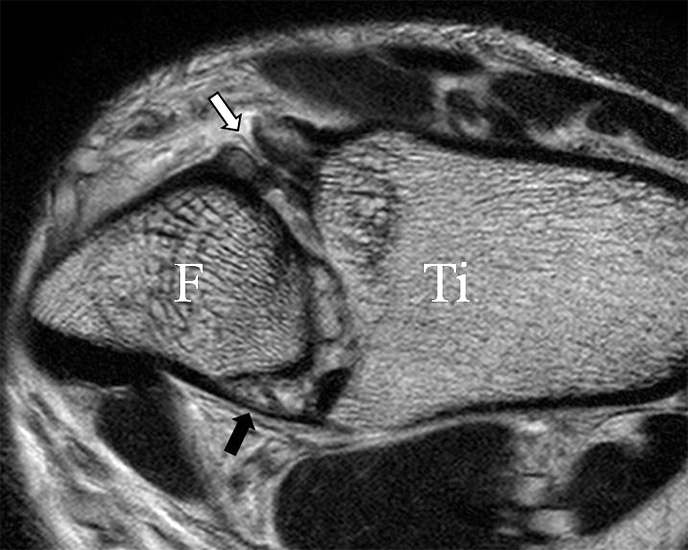

Der Ursprung des Ligamentum fibulocalcaneare liegt unmittelbar kaudal und dorsal des Ursprungs des Ligamentum fibulotalare anterius, so dass gehäuft kombinierte Verletzungen und auch ein gemeinsamer knöcherner Ausriss beobachtet werden. Nach kaudal dorsal verläuft das Band dann nach medial konvex unter die Peroneussehnen. Danach ist ein schräg deszendierender, gestreckter Verlauf bis zum calcanearen Ansatz abgrenzbar (Abb. 10). Dieser zu allen drei Standardebenen schräge Verlauf erschwert häufig die Diagnostik des LFC vor allem bei subtileren Verletzungen. Spezialprojektionen, die dem Bandverlauf orthograd folgen (entweder schräg coronar oder schräg sagittal) erleichtern auch hier die Diagnostik (Abb. 11) insbesondere nicht dislozierter Avulsionen. Assoziierte Verletzungen der Peroneussehnenloge müssen mit beurteilt werden, wobei neben Verletzungen der Sehnen und Sehnenscheiden die Beurteilung des Retinaculum peroneum superius und inferius wichtig ist. In einem Kollektiv von Patienten mit chronischen Außenbandinstabilitäten weisen 50% der Patienten eine Verletzung dieser Strukturen auf 5. Auch hier erleichtern hochauflösende Techniken die Diagnostik (Abb. 12).

Das Ligamentum fibulotalare anterius entspricht einer bifaszikulären Struktur (Abb. 2 a) mit interponierendem fibrovaskulärem Gewebe (S. K. Sarrafian (ed). 2003). Es gibt jedoch Variationen der Ligamentanatomie. In 55% liegt das LFTA als bifaszikuläres Band (Abb. 2 a), in 9% als monofaszikuläre Bandstruktur (Abb. 2 b) und in 36% als multifaszikuläre, striäre Variante (Abb. 2 c) vor 3.

Das LFTA verbindet die antero-inferiore Fibulaspitze mit dem Processus lateralis tali und inseriert hier an einem oder zwei kleinen Tuberkeln 3. Der in Neutralposition horizontale Verlauf erleichtert die kernspintomographische Darstellung in dieser Standardebene. Das LFTA weist durchschnittlich eine Breite von knapp über 2 mm auf 4. Somit sind bei einer Routinedarstellung in 3 mm Schichtdicke Anschnittsphänomene, die die Diagnostik erschweren, regelmäßig anzutreffen. Dementsprechend sind auch die ligamentären Subfaszikel nicht zu differenzieren. In koronarer Darstellung ist dies aufgrund der hohen Auflösung in der Schichtebene jedoch möglich (Abb. 2 a-c), wobei hier wiederum eine Integritätsbeurteilung des Bandes erschwert ist. Unter Verwendung hochauflösender Techniken im Millimeterbereich (Schichtdicke) sind hingegen auch in der axialen Ebene die subfaszikulären Strukturen zu beurteilen (Abb. 3).